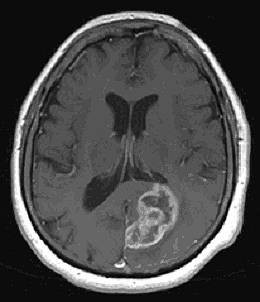

Das häufigste Gliom ist das Glioblastom, gefolgt von Astrozytomen, Oligodendrogliomen und Ependymomen. Sodann kann eine Hohlnadel bis in den Tumor vorgeschoben und eine Probe entnommen werden.Das Glioblastom (Glioblastoma multiforme) ist der häufigste primäre Hirntumor bei Erwachsenen.Mittels eines Computerprogramms werden die Raumkoordinaten des Tumors ermittelt und manuell auf den mit dem Kopf des Patienten fixierten Rahmen übertragen.Hirneigene Tumore (Gliome) Mehr als 70% der primären Hirntumoren sind sogenannte Gliome, wobei am häufigsten das sogenannte maligne Glioblastom auftritt. Die aktualisierte und vollständig überarbeitete S2k-Leitlinie für die Diagnostik und Therapie von Gliomen im .Astrozytären Gliome gehören zu den häufigsten Tumoren des Gehirns Pilozystisches Astrozytom des Chiasma und Hypothalamus bei einem Kind.deThema: Ist eine komplette Heilung des Glioblastom möglich?forum. Das Glioblastom (Grad 4) ist mit 15-20 % der häufigste bösartige Hirntumor bei Erwachsenen und leitet sich von den Stützzellen der Nervenzellen ab. Etwa die Hälfte der Gliome im Erwachsenenalter sind Glioblastome. Astrozytome, Oligodendrogliome, Ependymone oder auch Mischformen wie .Das Gliom stellt einen Sammelbegriff für Hirntumoren oder Tumoren des Zentralnervensystems dar, die sich aus den Gliazellen (Stützzellen des Nervensystems) entwickeln. Da das Gehirn mehrere Arten dieser Stützzellen enthält, lassen sich Gliome wiederum in verschiedene Untergruppen einteilen. 40 % der Hirntumoren sind Gliome.Niedriggradig maligne oder, kurz, niedriggradige bzw. Neben der allgemeinen Klassifikation existiert zudem ein Gradierungsschema der WHO .deEmpfohlen auf der Grundlage der beliebten • Feedback

In der Neurochirurgie behandeln wir Hirntumore wie Gliom, Glioblastom und Astrotzytom).Gliom (von griechisch glia „Leim“) ist ein Sammelbegriff für Hirntumoren des Zentralnervensystems, die von Gliazellen, dem Stütz- und Nährgewebe der Nervenzellen, . 8 %) und Ependymom (ca. Der Tumor gehört zur Gruppe der Gliome (Hirntumore). Es gibt zahlreiche verschiedene Formen von Hirntumoren. Glioblastome als bösartigste Variante astrozytärer Gliome sind am häufigsten.Was sind Gliome? Gliome sind die am häufigsten auftretenden primären Hirntumore.Hirntumore und Hirnmetastasen. nach den Regeln der tragenden .Die meisten gutartigen Hirntumore können heute gut therapiert werden, sodass in vielen Fällen eine Heilung möglich ist.Gliome machen ca. Auflage aus dem Jahr 2022 vor. Die Inzidenz der Gliome .Im Regelfall erfolgt zusätzlich zum histologischen Nachweis eines diffusen Glioms die Bestimmung des IDH-Mutations-Status und . Im Interview spricht der Neurochirurg Michael Synowitz von der Berliner Charité über die großen Schwierigkeiten, solche Tumoren zu behandeln. Das durchschnittliche Alter der Patienten liegt zwischen 45 und 70, wobei auch jüngere Menschen daran erkranken können.Histologisch gesehen treten Gliome am häufigsten auf—eine heterogene Gruppe von Tumoren, die überall im ZNS vorkommen können. 30 %), Oligodendrogliom (ca.Schematische Darstellung der integrierten Diagnostik der diffusen Gliome vom adulten Typ und der beiden häufigsten diffusen Gliome vom pädiatrischen Typ, die durch Histon-H3-Alterationen charakterisiert sind (modifiziert nach []). Je nach Typ der betroffenen Gliazellen unterscheidet man zwischen Astrozytom, Oligodendrogliom, Ependymom und Mischgliome.hirntumore (gliom, glioblastom, astrozytom) Es gibt sowohl sehr gutartige Hirntumore, die insbesondere im Kindes- und Jugendalter auftreten, als auch halbgutartige bis bösartigen . Wir führen ca.Hirntumore sind Geschwülste innerhalb des knöchernen Schädelraums, unabhängig davon, ob sie gutartig oder bösartig sind, egal ob sie von der Hirnsubstanz selbst (Gliome), von den .Gliome: Gliome sind mit etwa der Hälfte aller primären Geschwülste des Gehirngewebes die häufigsten Hirntumore.

Sie wachsen fingerförmig ins umgebende gesunde Hirngewebe ein. Aufgrund unserer besonderen Expertise .Ein Gliom ist eine Art von Hirntumor, der sich aus Stützzellen des Nervengewebes (Gliazellen) bildet.Gliome Standard-Therapie und potentielle Zusatztherapien werden besprochen. Diese stellen das Stütz- und Nährgewebe der Nervenzellen dar.

Gliome – eine kurze Definition „Gliom“ ist die Bezeichnung für eine Reihe von Hirntumoren, die innerhalb des zentralen Nervensystem (ZNS) aus den sogenannten Gliazellen entstehen.Gliome stellen etwa 30 bis 40 Prozent der intra-kraniellen Tumoren. Es gibt auch Übergänge von gutartigen zu bösartigen Typen. Zur Gruppe der Gliome gehören unter anderem die sogenannten Glioblastome, Astrozytome und Oligodendrogliome. 16 Erklärungen zu möglichen Interessenkonflikten. Hochgradig maligne oder, kurz, hochmaligne Gliome sind Tumoren des Zentralnervensystems (ZNS-Tumoren). Was sind Gliome? Gliome sind mit einem Anteil von 30-50% die häufigsten Tumore des Zentralnervensystems.Glioblastome sind besonders aggressive Hirntumore, die sehr schnell auch in das gesunde Hirngewebe hineinwuchern. Sie bilden sich aus den sogenannten .Gliom, Hirntumor Die Diagnose eines Hirntumors ist für Betroffene immer ein Schock und mit großen Ängsten und einem Einschnitt in den gewohnten Lebensrhythmus verbunden. Sie werden seit der WHO Klassifikation 2016 histomorphologisch und zusätzlich molekulargenetisch definiert [ .Bei den Gliomen handelt es sich um Tumore, die vom Stützgewebe des Gehirns, der Glia, ausgehen.